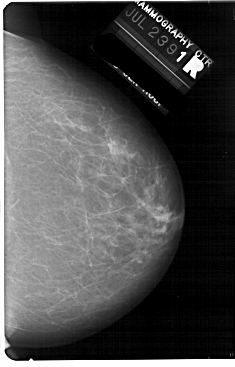

A_1738_1.RIGHT_MLO

RIGHT_CC LINES 5491 PIXELS_PER_LINE 3511 BITS_PER_PIXEL 12 RESOLUTION 43.5 NON_OVERLAY

RIGHT_MLO LINES 5491 PIXELS_PER_LINE 3691 BITS_PER_PIXEL 12 RESOLUTION 43.5 NON_OVERLAY